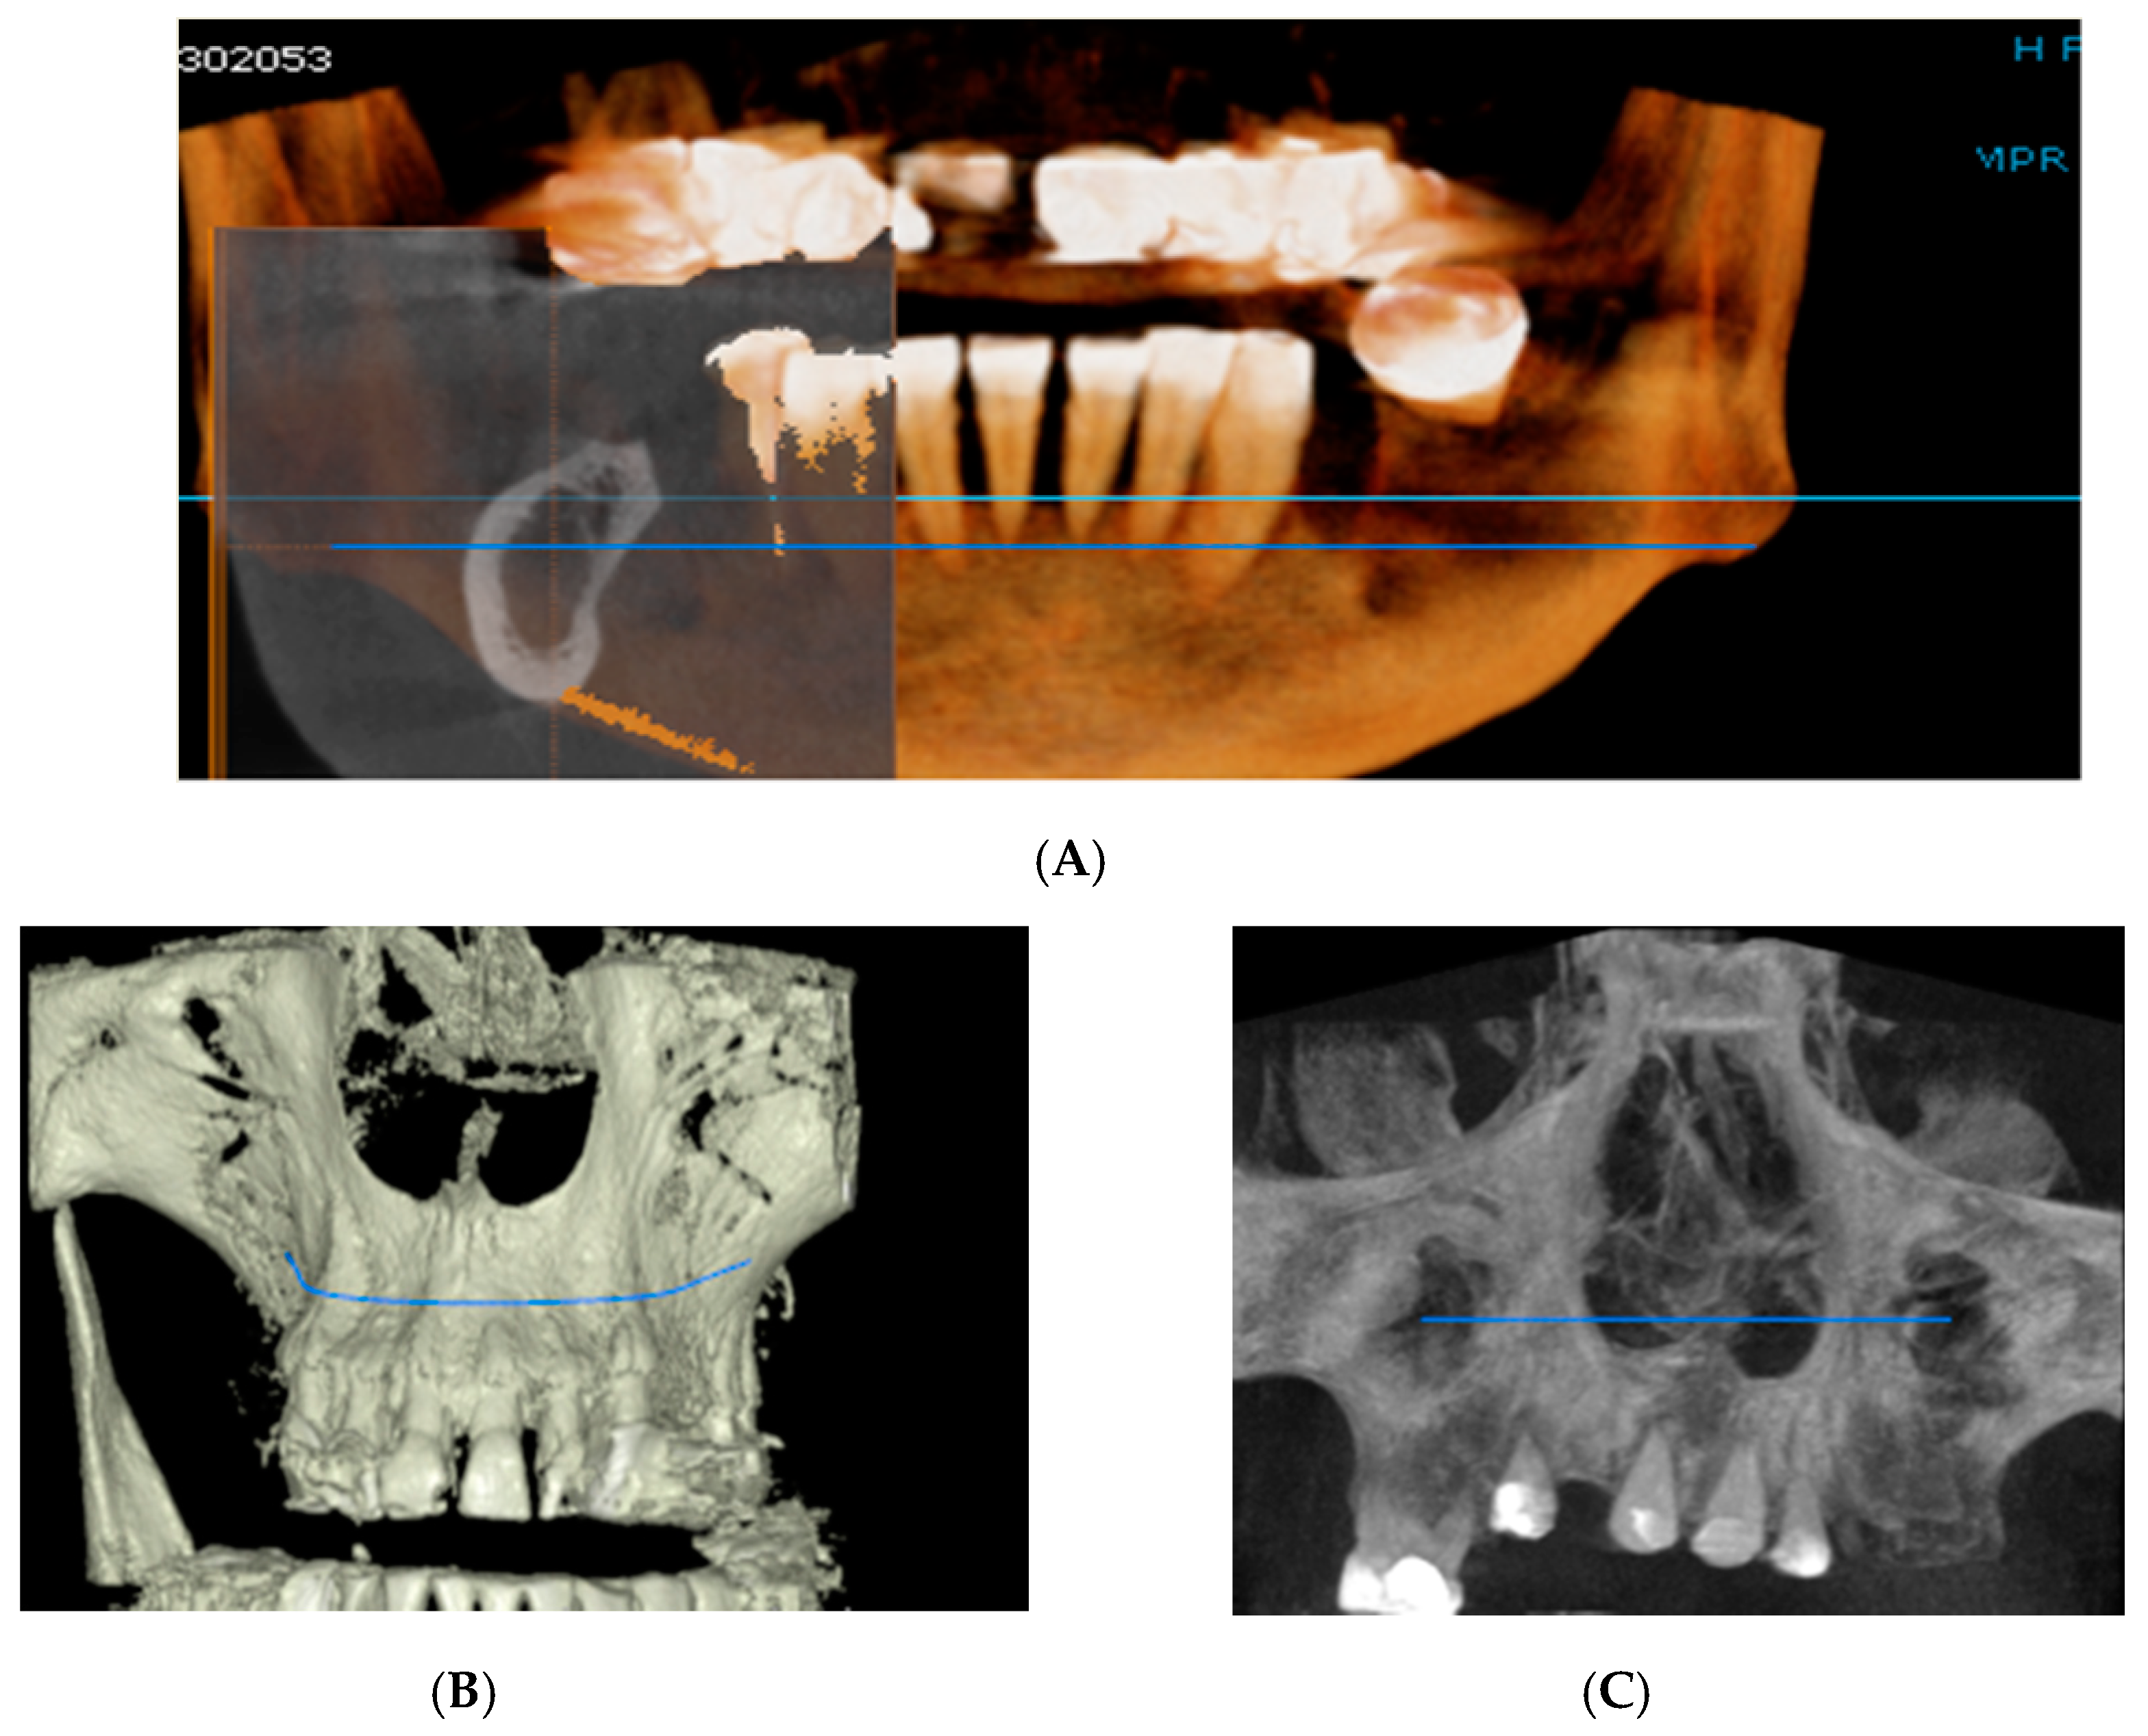

Figure 2.

Rendering images showing field of view (FOV) images used in the study. (A) Frontal view, (B) Frontal Bone view, (C) X-ray view.